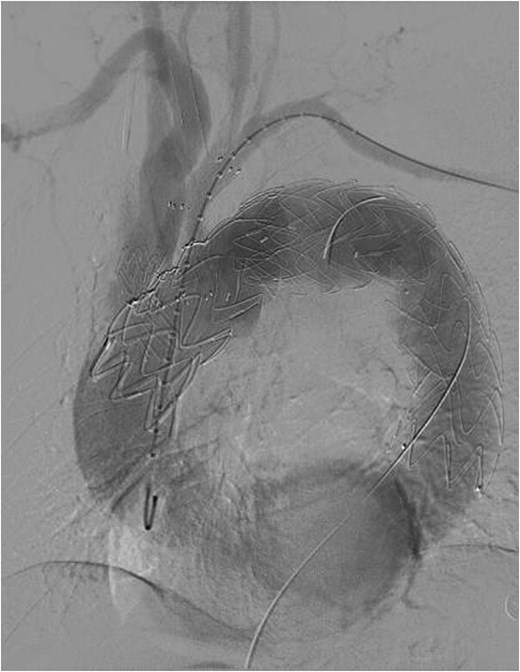

On March 1, 2024, the patient was readmitted for recurrent blood in phlegm. CTA revealed a type IV endoleak caused by membrane rupture. Angiography identified the endoleak at the stent graft junction (Fig. 8A). Controllable embolization coils were deployed to embolize the rupture. Post-surgery, symptoms disappeared (Fig. 8B).

(A) On March 1, 2024, the angiography showed endoleak (marked by arrows) at overlapping part of stent graft. (B) Dense embolization was performed on the residual breach of the stent graft membrane.